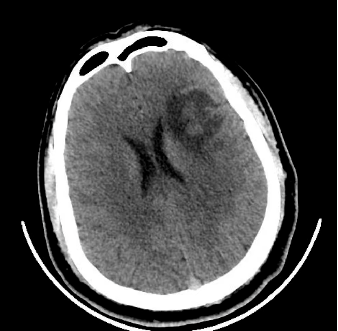

低级别弥漫性星形细胞瘤的影像学特征theneurosurgicalatlas全文翻译

弥漫性星形细胞瘤(ii级)